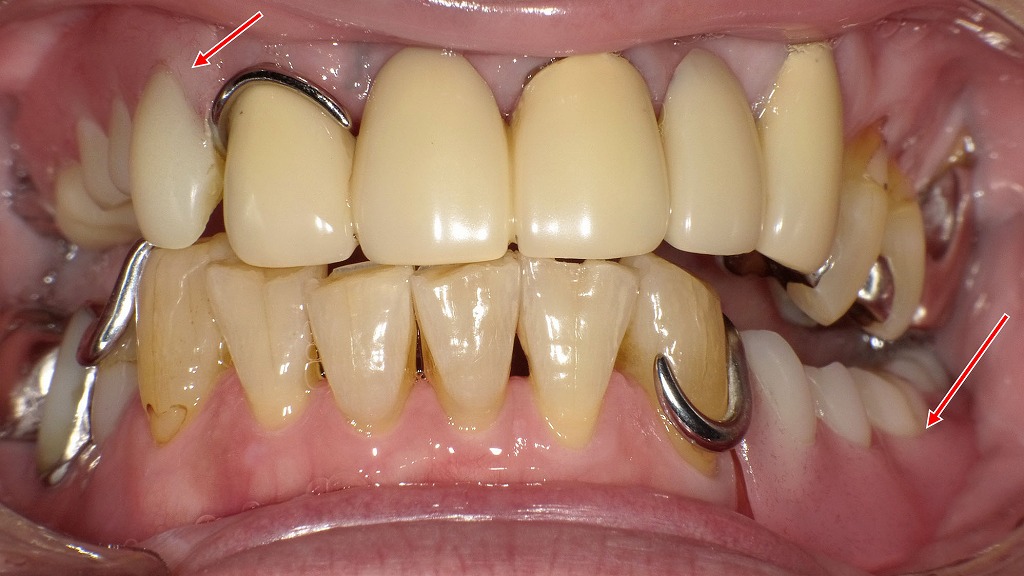

上下顎に保険適用のクラスプ義歯(部分入れ歯)が装着されている口腔内の状態です。入れ歯の適合が不十分だと、噛む力や舌・頬の動きが妨げられ、嚥下(飲み込み)機能の低下につながることがあります。歯科では、クラスプの形態や義歯の安定性、噛み合わせを細かく調整することで、食塊形成やスムーズな嚥下をサポートします。入れ歯の定期的な調整は、「食べる・飲み込む」機能を維持するうえで重要です。